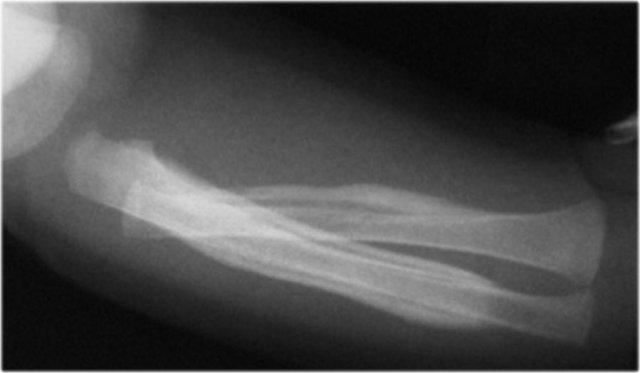

Gãy xương kiểu tay xách xô (Bucket handle fractures)

Gãy xương kiểu tay xách xô về bản chất giống với gãy xương góc.

Mảnh xương bị bong ra có kích thước lớn hơn và được nhìn thấy theo hướng “en face” (nhìn thẳng) như hình đĩa hoặc tay xách xô.

Hình ảnh

Gãy xương kiểu tay xách xô ở đầu trên xương chày. Mảnh gãy hành xương được nhìn thấy như hình đĩa hoặc tay xách xô.